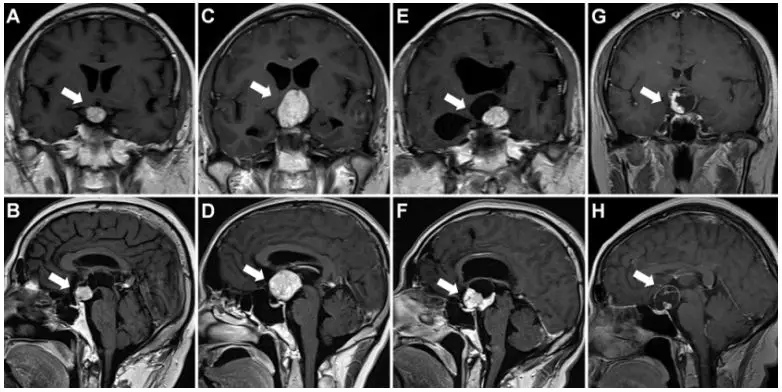

4.通过MRI成像识别BRAF突变型颅咽管瘤

Prediction of BRAF mutation status of craniopharyngioma using magnetic resonance imaging features.

PMID: 28984520 DOI: 10.3171/2017.4.JNS163113

通过52例颅咽管瘤患者的MRI特征,预测BRAF突变。经对比发现,BRAF突变型颅咽管瘤比BRAF野生型颅咽管瘤有更易鞍上生长、呈球型、主要为实质性结构、均匀强化和垂体柄增粗等显著的5个MRI表现特征。

【周川】